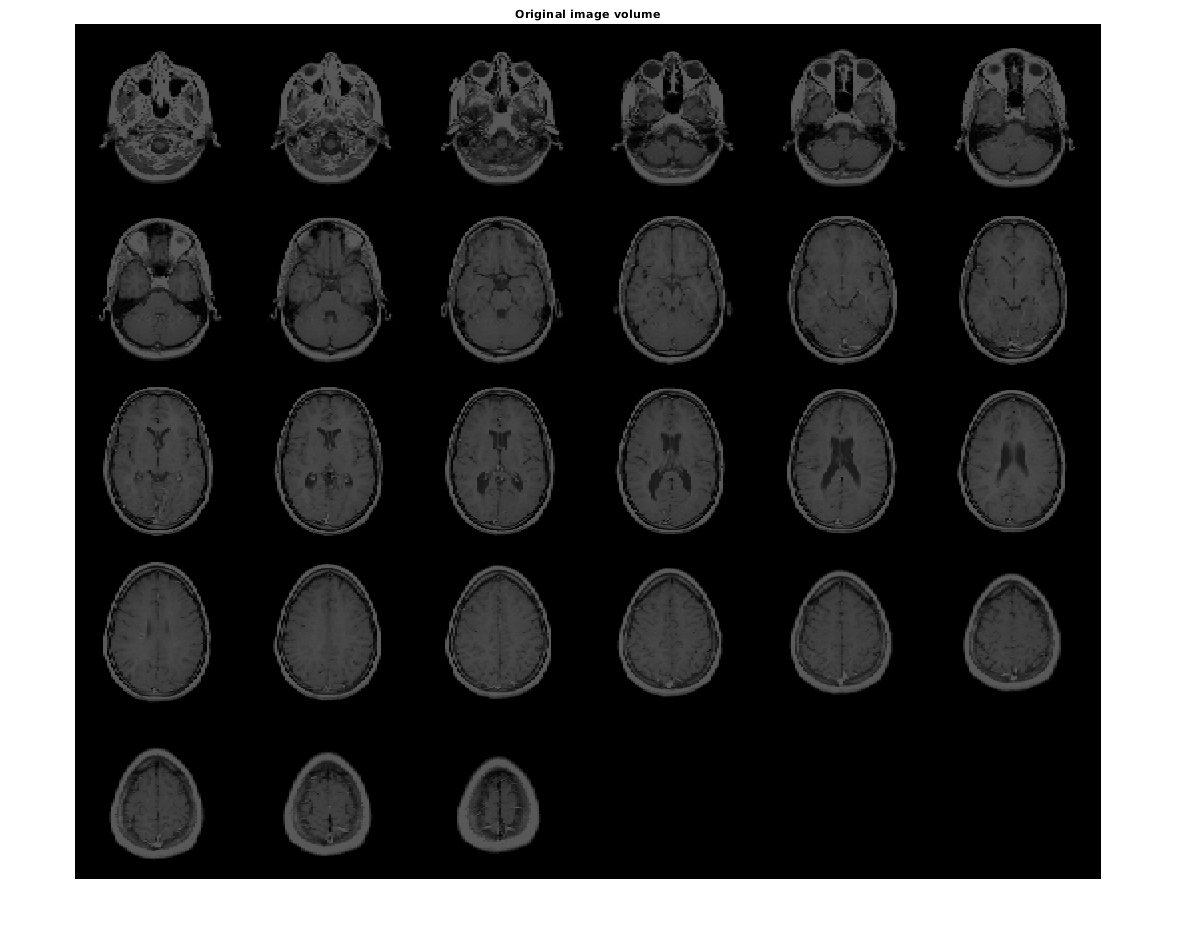

Загрузите данные MRI и отобразите их.

vol = load('mri');

figure

montage(vol.D)

title('Original image volume')

Figure contains an axes object. The axes object with title Original image volume contains an object of type image.